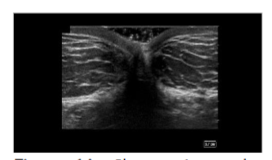

Cadavers were positioned supine. A global ultrasound scan was performed, starting at the umbilicus in short axis to the rectus abdominis, extending laterally to visualize the external and internal oblique muscles and their fascial junctions. The dermis, adipose layer, muscle layers, and bowel were identified to demarcate a safe adipose harvest zone.

The apical, mantle, and deep layers of the subcutaneous adipose compartment were distinguished, with the mantle and deep layers selected as preferred harvest targets due to their greater thickness. Depth markers on the ultrasound screen were used to measure adipose thickness and define the field size. Areas with potential umbilical hernias or fascial defects were identified and avoided. In clinical practice, Color Doppler can be employed to exclude vascular structures; however, it was not utilized in this cadaveric study.